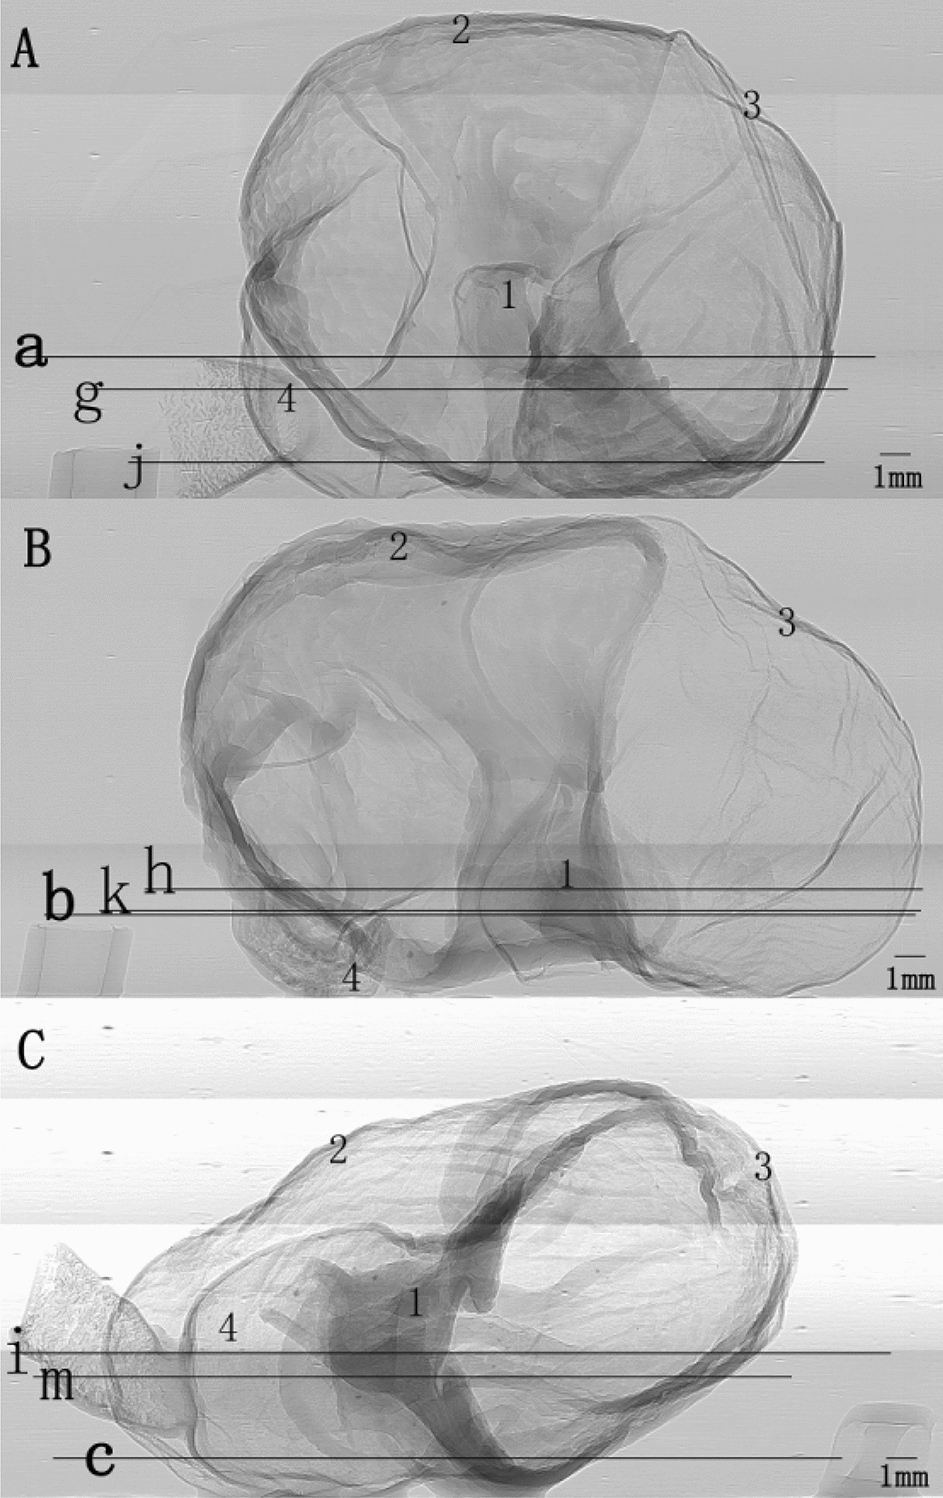

To intuitively understand the changes of gastric morphology and structure in different age groups, the XILPCI projection images of gastric specimens are shown in Fig. 1. Changes were observed at different week in rats. Figure 1A shows the ordered and regular tissues of a 4-week-old young gastric normal specimen, and the gastric walls are smooth without any hyperplasia. The XILPCI image are more detailed than the X-ray traditional image of a normal gastric specimen [5–8], as we could only see the overlapping walls of the stomach in the absorption images, and the images are very fuzzy with an unclear internal texture (as shown in Fig. 2).

Fig. 1.

XILPCI projection images of rats’ gastric specimens. A A 4-week-old specimen showing a smooth gastric corpus wall. B A 6-week-old specimen showing the uneven gastric walls inside the stomach. C A 12-week-old specimen showing thick gastric corpus walls and more gastric corpus wrinkles. 1 Cardia, 2 Gastric Corpus, 3 Gastric Fundus, 4 Pylorus

On XILPCI images, a 4-week-old image shows a uniform grey level, which indicates that the wall of the 4-week-old gastric corpus is as thick as the gastric fundus. It is obvious that the wrinkles of the fundus are abundant, while the gastric fundus is much thinner. In the middle of Fig. 1B, C, there is a demarcation line between the gastric corpus and the gastric fundus. Figure 1B demonstrates the characteristics of a 6-week-old adult gastric normal specimen XILPCI image. The gastric wrinkles are more extensive, but the wrinkles of the 6-week-old gastric fundus are fewer than those of the 4-week-old gastric fundus, as shown in the image that the grey of a 6-week-old gastric fundus is lighter than that of a 4-week-old fundus. The 6-week-old gastric corpus is thicker than the 4-week-old gastric corpus for the grey of a 6-week-old gastric corpus is deeper in image than that of 4-week-old. Figure 1C demonstrates the characteristics of mature gastric normal tissues from a 12-week-old normal gastric specimen. The wrinkles in the walls of the gastric corpus and duodenum are the most abundant.

Twenty-one Sprague–Dawley healthy male rats were purchased from the Animal Centre of Capital Medical University in China. The rats were randomly divided into three groups with seven rats in each one. The rats were housed in cages under a controlled temperature of 22.0 ± 1.0 °C and 12-h light–dark cycles. They were fed on standard laboratory chow and water and allowed to acclimate for more than 7 days. The rats were starved for 12 h and killed under anesthesia with an intraperitoneal injection of pentobarbital sodium at 4, 6 and 12 weeks of age. The stomach of the rat was removed and the stomach cavity is filled with 10% formalin to maintain the morphological structure of the stomach for X-ray image scanning. Stomach specimens were shown Fig. 8. These stomach tissues were cleaned with normal saline, fixed in 10% neutral phosphate-buffered formalin solution for 24 h and embedded in paraffin. 5 μm thick of the specimens were obtained from the stomach and stained with HE staining. This animal study was in strict accordance with the recommendations in the Guide for the Care and Use of Laboratory Animals of the National Institutes of Health. The animal welfare Committee on the Ethics of Animal Experiments of Capital Medical University (Protocol No. AEEI-2016–079) approved the experiment protocol. All surgeries were performed under pentobarbital sodium anesthesia, and all efforts were made to minimize suffering.

Fig. 8.

Rats’ gastric specimens. A A 4-week-old gastric specimen. B A 6-week-old gastric specimen. C A 12-week-old gastric specimen. 1 Cardia, 2 Gastric Corpus, 3 Gastric Fundus, 4 Pylorus. All the positions have been noted on the gross anatomy